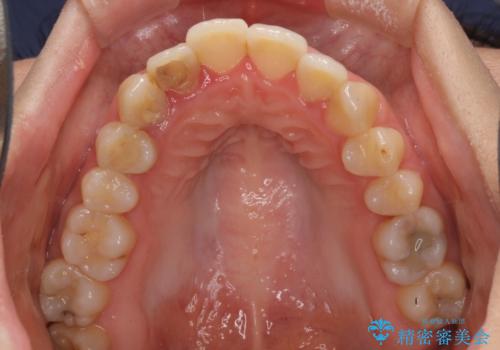

開咬と前突を改善 ワイヤー装置での抜歯矯正

元々むし歯の処置歯が多く、神経を取り除いている歯が多くありましたが、どうやら右上の前歯と小臼歯は外傷により神経を失った可能性があり、抜歯したスペース前後の歯が全く動かない状態でした。

結果として下顎の小臼歯は抜歯せず、右上の抜歯スペースはむし歯処置を兼ねてオールセラミックブリッジにて補綴治療を行うこととしました。

動かない歯での停滞や、出産と子育てなどにより治療期間は長期化しましたが、整った歯列にて仕上げることができました。